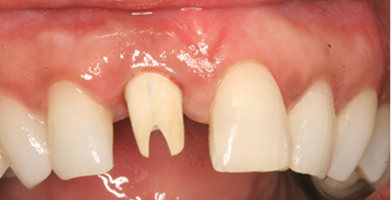

Single Implants

Ideal for replacing one missing tooth without affecting surrounding teeth.

BEFORE

AFTER